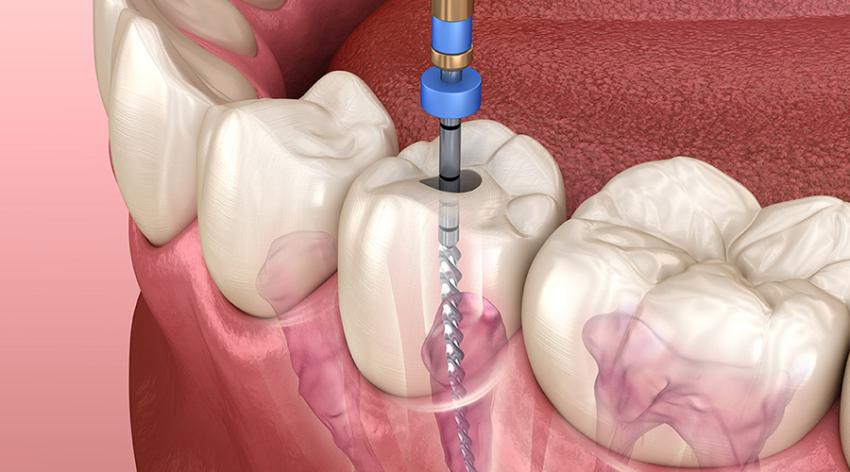

Root canal therapy, so feared for its allegedly painful aspects, is a highly effective and relatively pain-free procedure when performed by a skilled dentist. The procedure itself is elimination of infected or destroyed pulp inside a tooth, disinfecting and cleaning out the area, and sealing so that infection cannot be re-established. Done correctly, it saves the natural tooth, eliminates pain, and returns function to normal.

What do you want in a best root canal dentist? Experience and specialty first. Dentists who specialize in endodontics or who have done hundreds of successful root canals under their belts are better equipped to handle tricky situations. They probably also have the latest technology such as rotary endodontics, digital X-rays, and dental microscopes, which enhance precision and reduce discomfort.

And yet another significant aspect is the presence of the most recent dental technology. The dental clinics with the most recent technology in Paschim Vihar are capable of delivering better results in the least possible time. Procedures like painless anesthesia, digital x-rays, and one-visit root canals truly boost patient satisfaction.